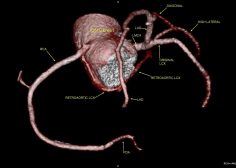

36Y male with chest pain, CT coronary shows a very rare anomaly. Twin LCX, (less than 10 cases in literature ).

The original LCX originates from LMCA , it supplies an early OM.

The 2nd anomalous LCX (arises from proximal RCA) with retro-aortic course till it reaches the left AV groove where it supplies a small OM.